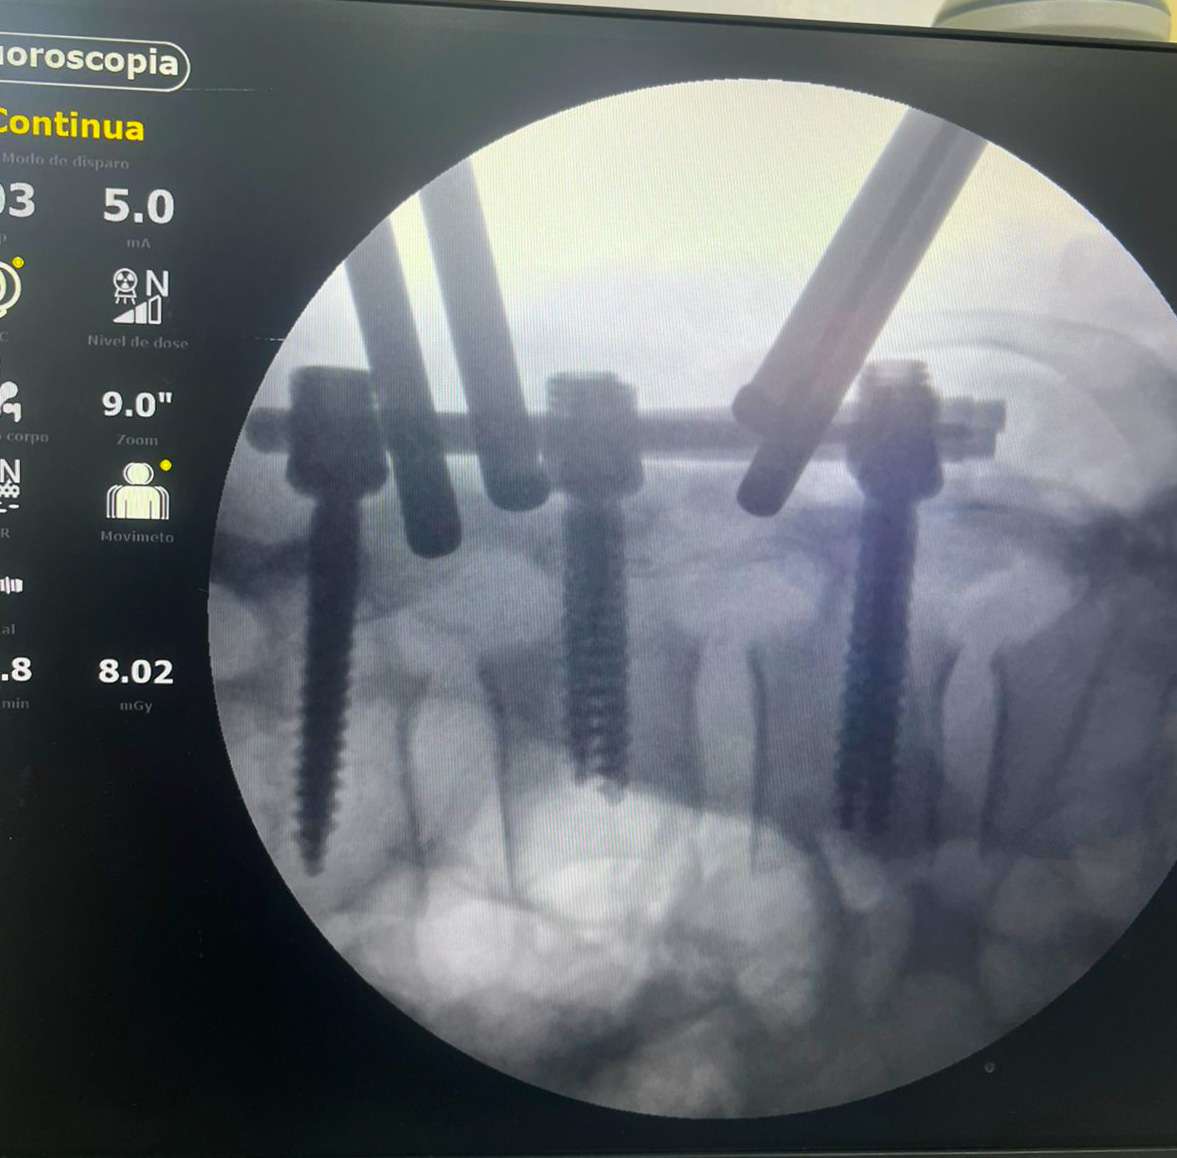

O paciente, Luciano Francisco, de 41 anos, foi atropelado por um carro na madrugada de sábado, enquanto se dirigia ao trabalho de bicicleta. Com o impacto, ele sofreu uma fratura na coluna lombar e perdeu os movimentos dos membros inferiores. Diante da gravidade do quadro, a equipe médica interviu com agilidade e organizou a realização da cirurgia já no dia seguinte, ontem domingo (8).

O procedimento, que durou 1h45, foi conduzido pelos ortopedistas especialistas em coluna, doutor Marlon Mendonça e Paulo Splenger, com apoio da equipe de trauma da unidade. Segundo o médico, a cirurgia transcorreu com sucesso e sem intercorrências. “O paciente chegou lúcido à UTI e já estava conversando após o procedimento. A expectativa agora é acompanhar a evolução neurológica, que depende do tempo e da resposta do organismo”, explicou doutor Marlon.

A intervenção teve como objetivo a descompressão da medula e a estabilização da coluna, medidas urgentes para minimizar os danos causados pelo trauma. “É um marco. Iniciamos um novo capítulo para o hospital, com a realização de cirurgias de alta complexidade que antes não eram possíveis. Isso representa mais qualidade, mais dignidade e menos sofrimento para os nossos pacientes”, afirmou doutor Paulo Splenger.